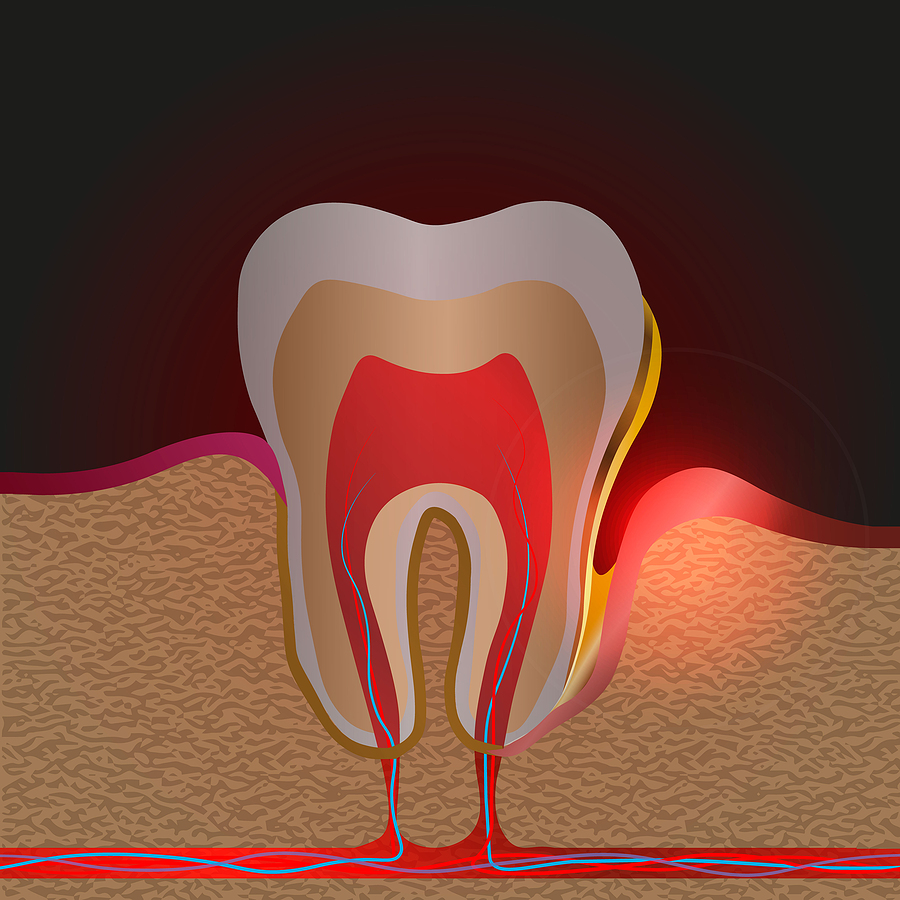

■ 楔上欠損とは?

歯と歯ぐきの境目(歯頸部)にできる、くさび状のへこみのことです。

■ なぜ歯の根元に起こるの?

歯の根元は、エナメル質が薄く、力が集中しやすい構造になっています。

そのため、負担が蓄積すると、くさび状に欠けてしまうのです。